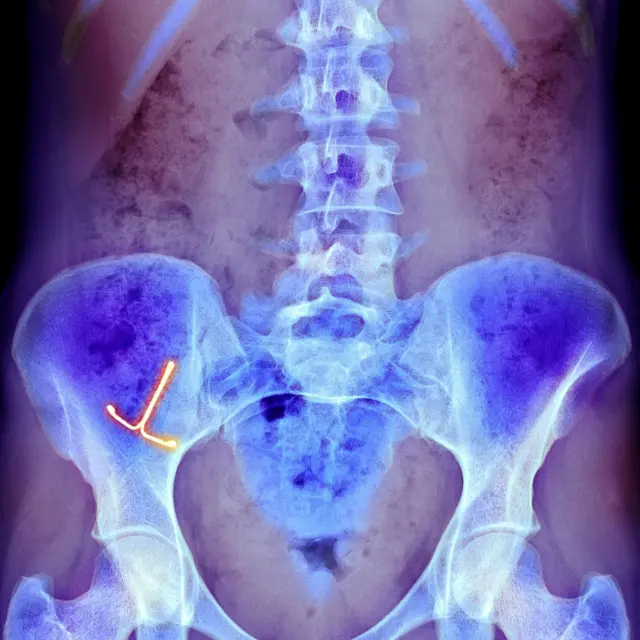

Los cuerpos extraños dentro de la vagina pueden ser aquellos que son médicamente necesarios y aquellos que están allí por otras razones.

Los típicos objetos extraños vaginales incluyen pesarios o dispositivos anticonceptivos intrauterinos dañados que la paciente puede haber olvidado, o que no se haya dado cuenta de que están dañados.

Estos representan riesgos a largo plazo en forma de infecciones, fístulas (una apertura anormal entre un órgano hueco y otro o entre un órgano hueco y la superficie de la piel), y la formación de cálculos.